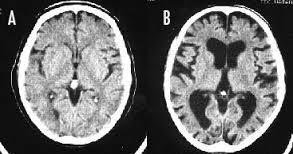

喫煙すると頭が悪くなるのは本当です。 長期の喫煙により大脳皮質が薄くなり、認知機能が低下してしまうのです。 画像Aは喫煙しない人の脳、画像Bは喫煙者の脳です。 画像Aの脳と比べて、画像Bの脳は萎縮して隙間だらけになっています。 喫煙をやめても元の状態まで回復するのに数十年かかるそうです。

--- 「喫煙者の脳」やはり異変が起きていた(石田雅彦) - Yahoo!ニュース ---

タバコを吸うと脳がすっきりするのは真っ赤な嘘だ。研究によれば喫煙者の脳では明らかに異常が起きている。認知機能も低下し、大脳皮質が元に戻るのには25年もかかる。一刻も早くタバコなど止めたほうがいい。